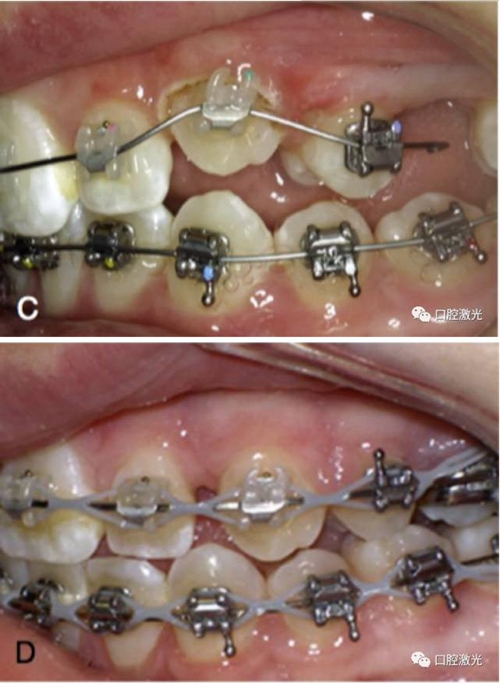

有時,會遇到一些口腔衛(wèi)生問題比較嚴重的患者,從而導致牙齦發(fā)炎而腫大。通過改善口腔衛(wèi)生環(huán)境,炎癥可以得到緩解,但增生的牙齦不一定都可以完全恢復。下圖的患者就存在口腔牙齦肥厚問題,同時左上部犬牙存在部分萌出的問題,右上部犬牙存在未萌出問題,這些問題都妨礙了托槽的粘接。因此,實施了全口腔的牙齦整形手術(shù)。去除了多余的牙齦組織,增加了犬牙的暴露面積,從而使托槽的粘接更為便利,同時也提升了患者保持口腔衛(wèi)生的狀況。

治療前

激光牙齦整形后即刻

激光治療當天粘接托槽

6周后效果